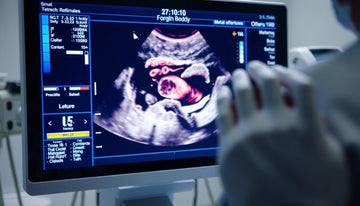

Ultrasound imaging serves as a valuable tool in medical diagnostics, allowing healthcare professionals to visualize various bodily structures in real-time. When an ultrasound shows a foreign body, it can raise important questions for patients about the implications and next steps to take. Understanding what this finding means, why it may occur, and how to approach it is vital for informed decision-making. This article aims to provide essential insights regarding ultrasound findings of foreign bodies, common causes, implications, and suggested actions following such results.

When ultrasound imaging is ordered by a licensed medical professional, it serves as a vital tool to visualize soft tissues, including tendons, muscles, ligaments, and other structures within the body. Specifically, when an ultrasound shows a foreign body, this refers to the detection of an object that is not normally present in the body, which could be a splinter, shard, or any other material that has entered the tissue. The results from the ultrasound imaging will be interpreted in conjunction with physical assessments and clinical symptoms to form a comprehensive understanding. It is essential to note that while ultrasound can reveal structural details, it does not assess pain levels or functional capability directly. Therefore, any diagnosis or treatment plan should be guided by a qualified healthcare provider, as ultrasound findings alone do not predict outcomes or recovery timelines.

When an ultrasound shows a foreign body, it typically indicates the presence of an object that is not naturally part of the body, such as shards of glass, metal fragments, or other materials. This finding can occur due to various reasons, including accidental injury, surgical procedures, or previous trauma. The ultrasound serves as a non-invasive imaging method to visualize soft tissue and foreign materials within the body, allowing healthcare providers to evaluate the exact location and characteristics of the foreign body. Understanding the potential sources of these findings contributes to a comprehensive assessment and aids clinicians in determining the best approach for management.